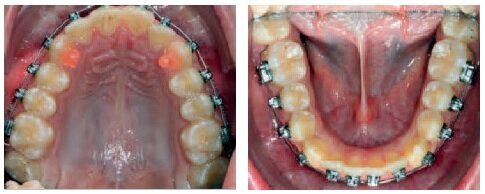

VISIT NO 1

Both appliances bonded on the same day.

SAP bracket placement

Torque Selection

Maxilla: Super low torque on the incisors – super torque on the canines.

Mandible: Low torque on the incisors – super torque on the canines.

014 CN archwires were placed along both arches, from the 1st molar to the 1st molar, without stops.

Bite turbos were bonded to 13 – 23 in order to unlock the occlusion, promote leveling, and protect the brackets on the lower arch.